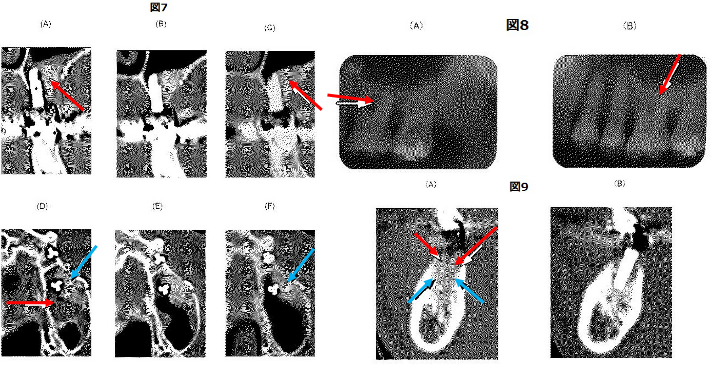

結果を表6、図7(A)〜(F)、図8(A)及び(B)、並びに図9(A)及び(B)に示す。

図7(A)では、白抜き矢印①で示した部分にβ-TCPの粉末が詰まっていることが観察された。

これに対し、図7(C)では同じ部分が矢印②で示した部分の構造が変化し、下側にある骨と同じ無構造となっており、骨形成が促進されていることが確認された。

また、図7(D)では、白抜き矢印の部分①に骨ではなく、され肉芽組織が形成ていること、及び黒色の矢印の部分②に未熟な骨芽形成されていることが観察された。

これに対し、図7(F)では黒食の矢印③の部分が成熟した骨となっており、骨形成が促進されていることが確認された。

以上から、歯科の分野における骨形成の促進が確認された。

インプラントでは、図7〜図9に示すように、いずれの症例においても骨の再形成が観察された。

また、足場としてβ-TCPを使用したときに、β-TCPの骨への置換等がどのように起こっているかを、提出組織をヘマトキシリン及びエオシンで染色して確認した。